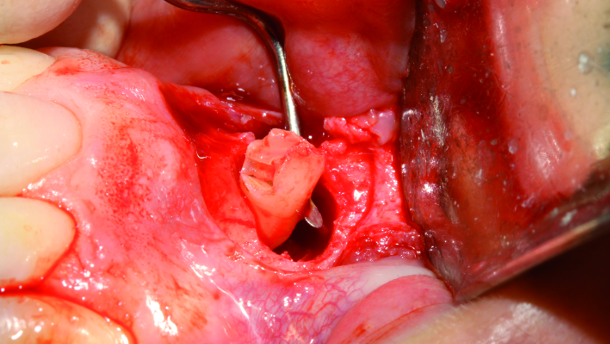

The oedematous pedicle that was compressed by the erupting follicle of the supernumerary tooth and caused a lack of blood supply to the pulp of the left central incisor can be observed in the image, held by a haemostat (Fig. 14).